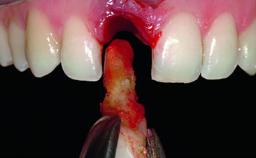

Replacement of a Missing Upper Left Central Incisor, Late Placement of an RC Bone Level Implant and Adjacent Tooth Restoration

A healthy 38-year-old male patient was referred for replacement of a failing tooth-supported cantilever fixed dental prosthesis on teeth 11 and 21. The patient reported a history of trauma at 13 years of age that had resulted in the subsequent loss of tooth 11, as well as endodontic treatment of the adjacent abutment tooth 21. A metal-ceramic cantilever fixed dental prosthesis replacing tooth 11 had been provided by his general dentist several years after the loss of the tooth, with tooth 21 as the sole abutment. At the time of initial presentation, this restoration had been in service for over 20 years.